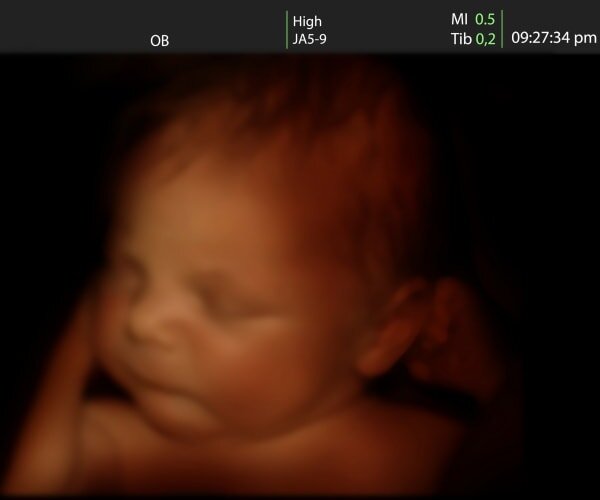

واکنش جنین در رحم مادر به مزه و بو

محققان با بررسی سونوگرافیهای چهار بعدی میگویند جنین به بو و مزه مواد غذایی که مادر در دوران بارداری میخورد، واکنش نشان میدهد. آنها معتقدند تغذیه مادر بر عادات غذایی آینده کودک هم تاثیرگذار است.